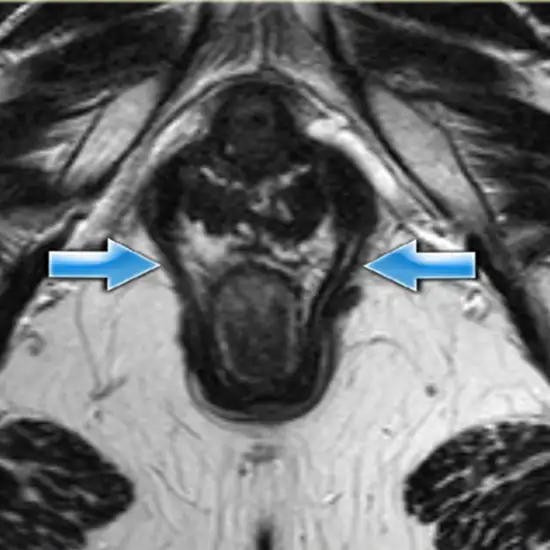

MRI for Fistulogram images the sphincter muscles, anal canal, and surrounding soft tissues. A fistula is an irregular channel connecting two usually unconnected organs or arteries. The most typical location for a fistula is around the anus, between the vagina and rectum, or intestine and skin. Redness, swelling, and skin irritation around the anus are common fistula symptoms.

MRI (Magnetic Resonance Imaging) screening of the Fistulography is a non-invasive radiology test used to evaluate the condition of the sphincter muscles of the anal and surrounding tissue. MRI Fistulography is done to look for sphincter muscles of the anal and the surrounding area.